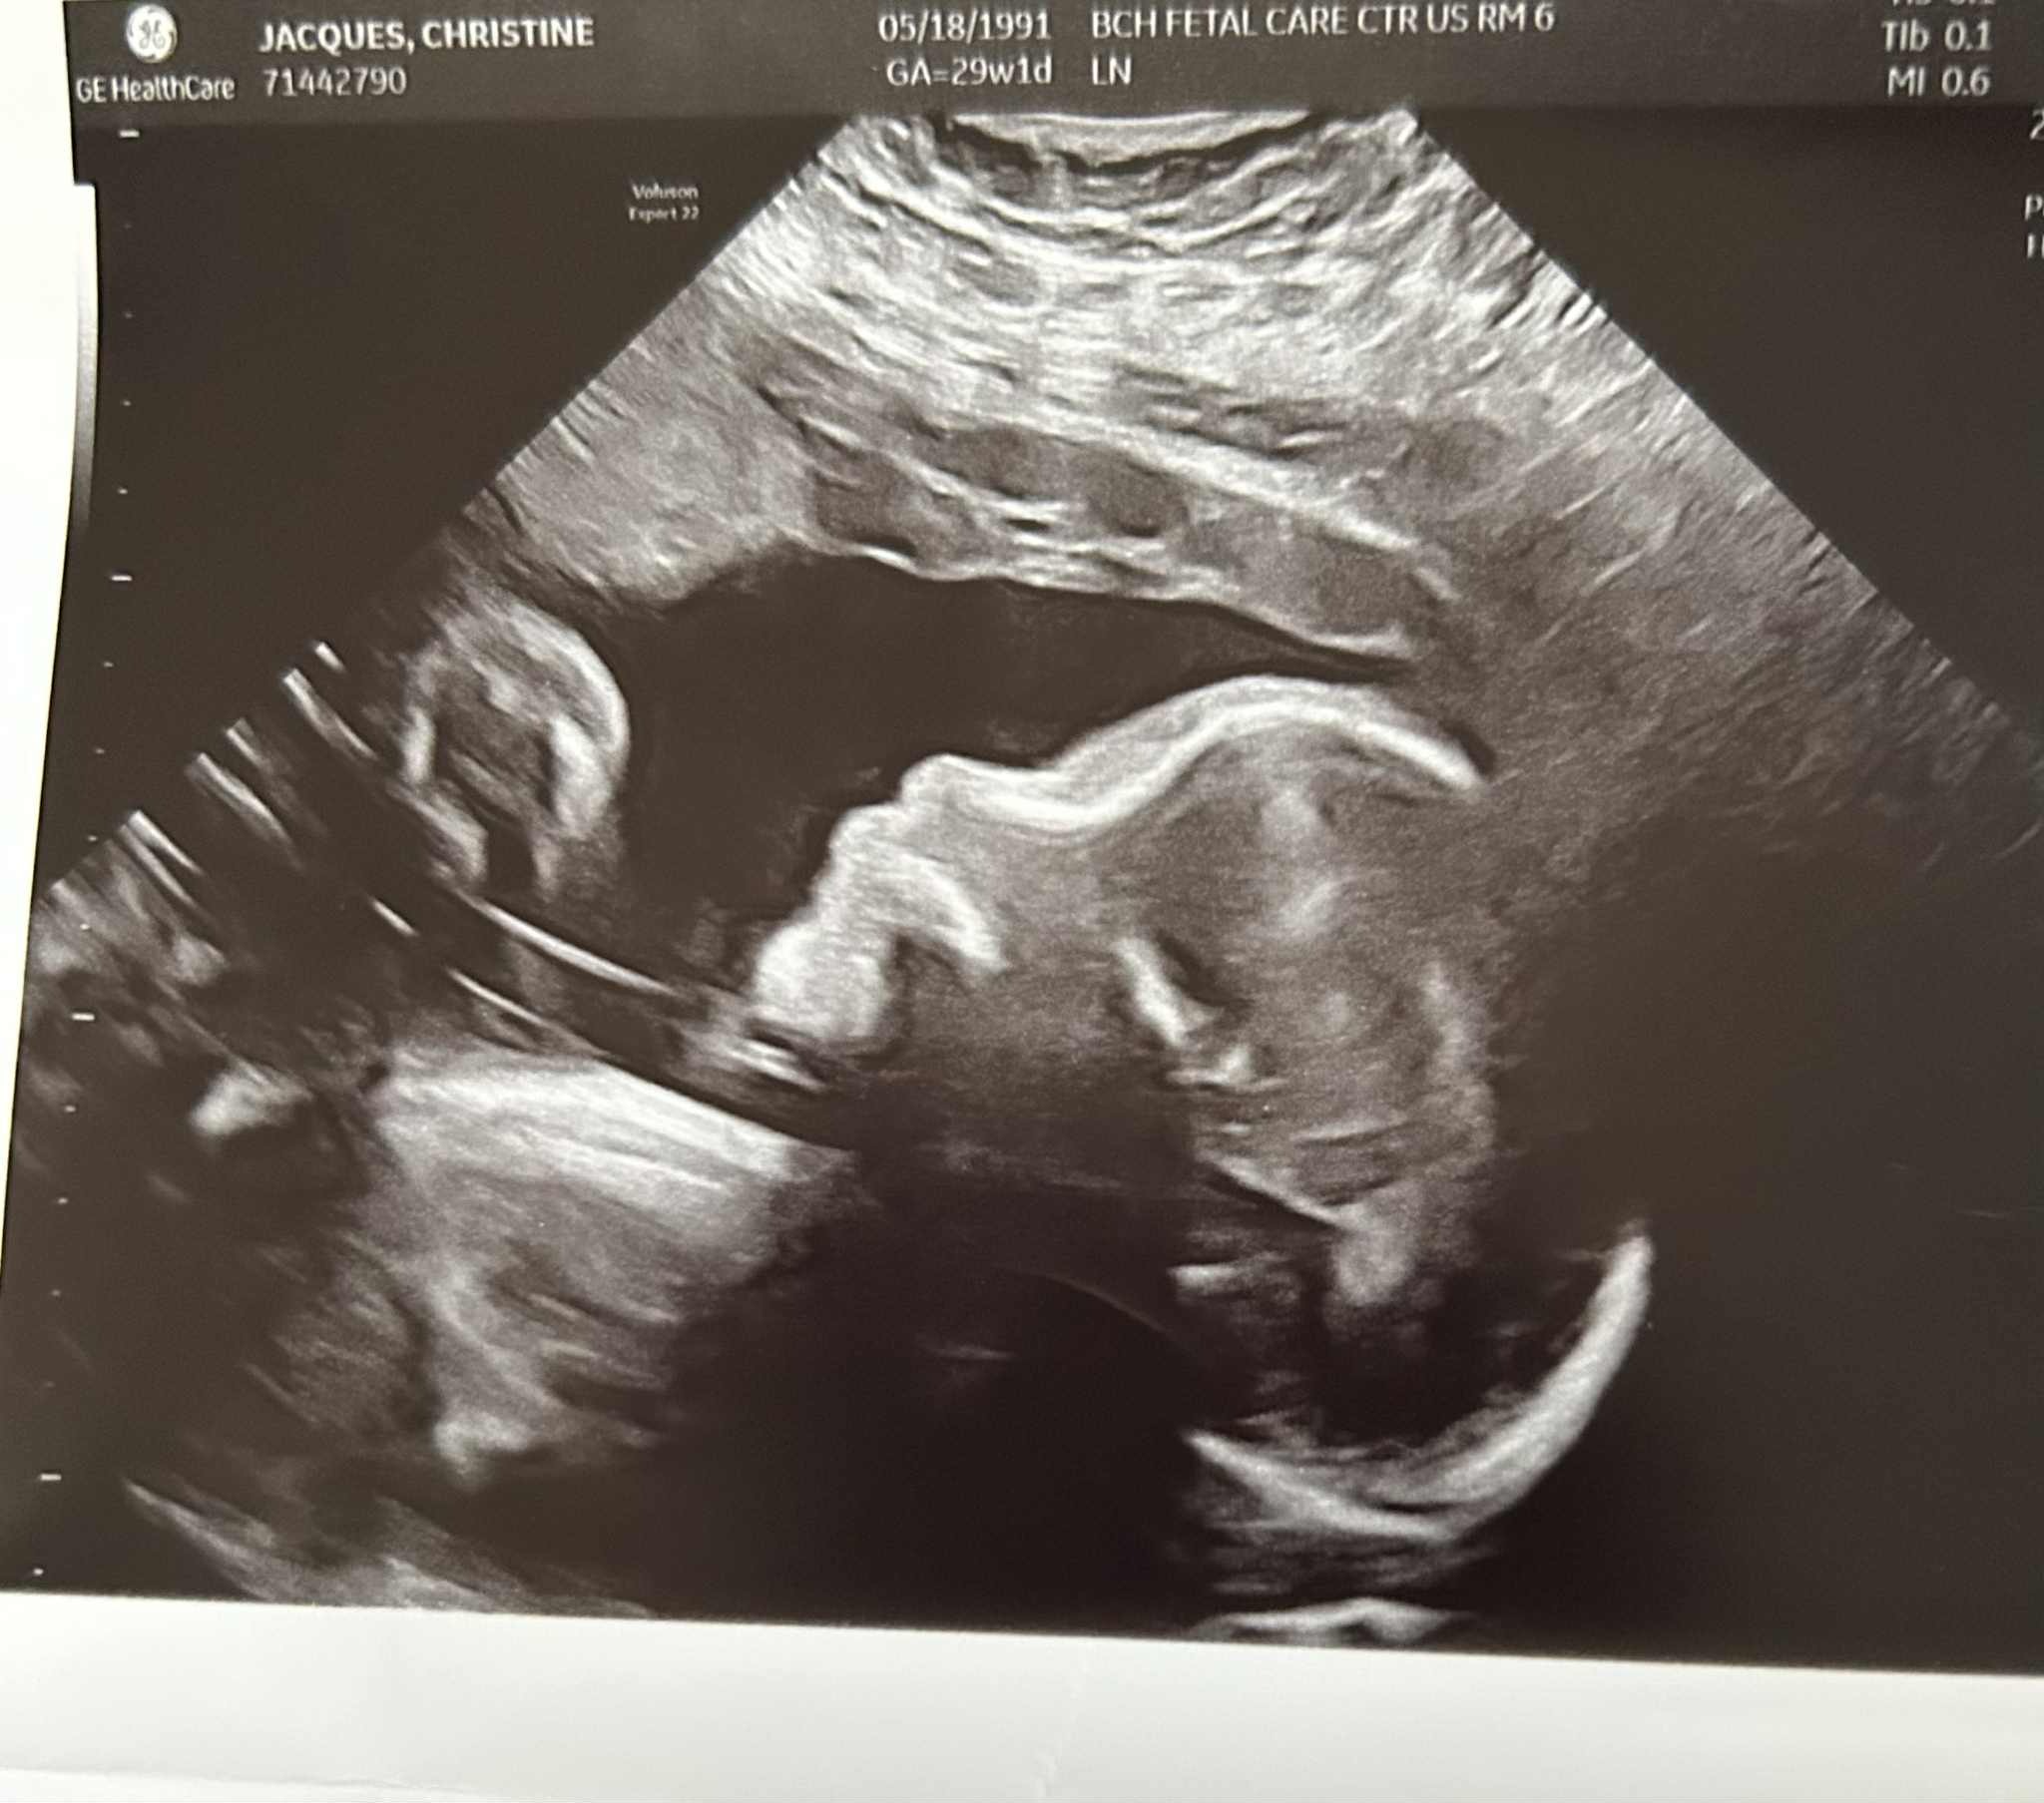

I am writing this on behalf of a beautiful young couple Roland Scott and Christine Jacques who are expecting their 1st baby boy who has a serious and potentially fatal defect call Congenital Diaghragmatic Hernia (CDH). The severity of the condition will require the baby to be placed on a heart and lung bypass (ECMO) and undergo surgery shortly after birth. It may be several months before the baby will be able to leave Boston Childrens Hospital, the process of recovery will take years, and the doctors will need to monitor until he is a fully grown adult.